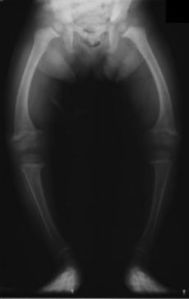

من المعروف أن فيتامين (د) من الفيتامينات المهمة التي يحذر الأطباء من نقصانها، خاصة عند الأطفال. فنقصان هذا الفيتامين يؤدي الى الكساح عند الأطفال. الكساح (Rickets) هو ضعف في العظام يؤدي الى تشوهات بها وكسور. هذا الضعف ينتج عن نقص في فيتامين (د) أو الفسفور أو الكالسيوم الذين يحتاجهم الطفل بشدة أثناء النمو لبناء عظام قوية سليمة. فيتامين (د) أيضا له دور في النمو السليم وفي الحماية من الالتهاب الرئوي وأمراض القلب والسكر والمناعة والأسنان.

50da3-230px-xrayricketslegssmall

انحناء العظام في الكساح